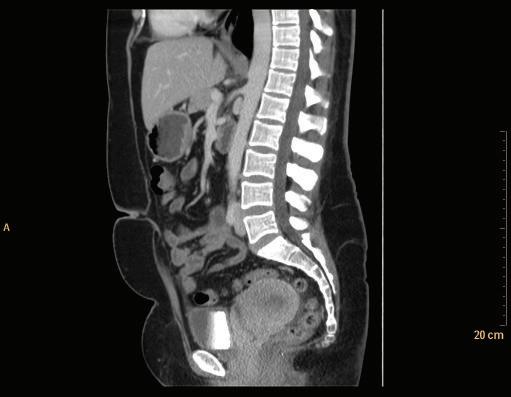

Sagittal CT images are shown as though the patient is looking toward the viewer’s left (Fig. 1-19).

FIGURE 1-19 Sagittal CT of the abdomen.